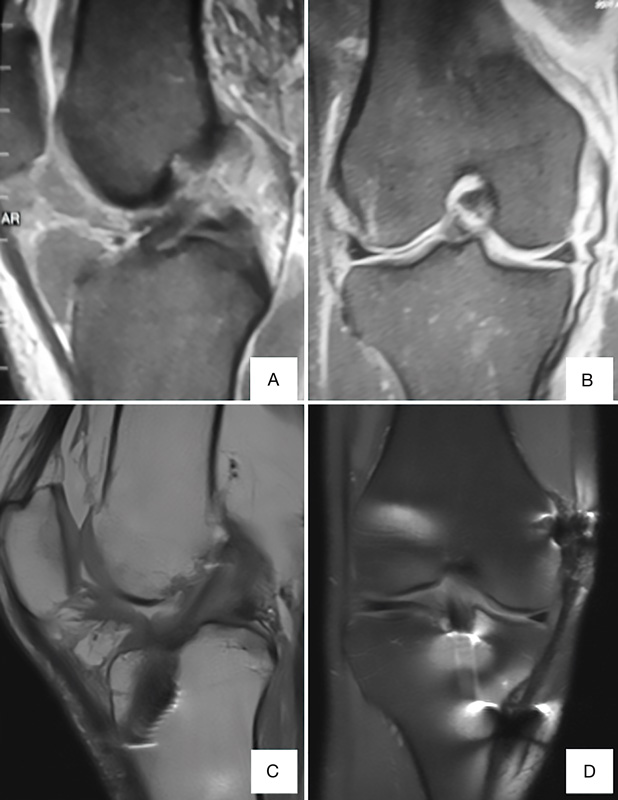

Figura 1. Reconstrucción del ligamento colateral medial. A: desinserción proximal de semitendinoso con extractor de isquiotiables abierto, manteniendo inserción distal; B: tunelización de semitendinoso; C: sitio de fijación femoral (grapa); D: sitio de fijación tibial. Distal a 6 cm de superficie articular (grapa). Proximal a 1,5 cm de superficie articular (sutura).